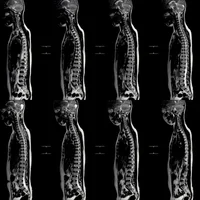

Hydrocéphalie